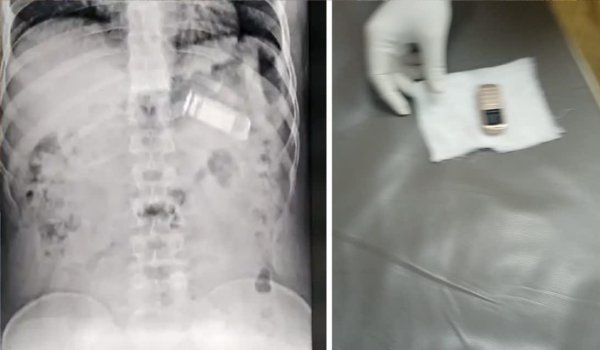

प्राप्त जानकारी के अनुसार जयपुर जेल में कैदी फज्जू खान ने मोबाइल फोन छिपाने की नियत से मोबाइल फोन को ही निगल लिया था, जिसे बाद में जयपुर के सवाईमानसिंह अस्पताल के चिकित्सकों ने बिना आपरेशन एन्डोस्कोपी विधि से निकाल लिया था।